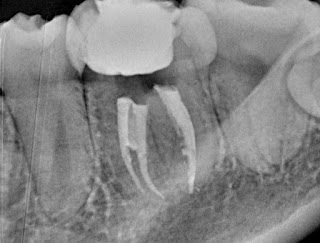

Localizamos los conductos mesio-vestibular, mesio-lingual y distal y hallamos sus longitudes de trabajo con limas K #10 y localizador de ápices Root ZX Mini siendo de 19 mm en todos ellos. Además, observamos un claro istmo de unión entre los dos conductos mesiales en el tercio coronal. Según la revisión publicada por Valencia de Pablo y col. en 2010 sobre el primer molar inferior permanente, la incidencia de estos istmos en la raíz mesial puede ser hasta del 55%.

Por último, limpiamos la cámara pulpar con alcohol etílico 96º, colocamos una bolita de algodón y la obturación provisional de Cavit y realizamos radiografías finales: una ortorradial y otra distorradial, en la que podemos observar la obturación del istmo de la raíz mesial.